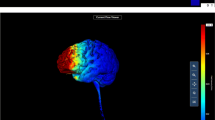

Participants were randomly assigned to receive anodal tDCS or sham stimulation over the rVLPFC. To stimulate that region, direct current was applied using a constant current regulator (DC-STIMULATOR; NeuroConn GmbH, Germany). A pair of saline-soaked sponge electrodes were applied to the participant’s scalp. The anode electrode was placed over F6 (MNI coordinates: 58, 30, 8), whereas the cathode electrode was placed over the controlateral supraorbital area. To increase the focality of the stimulation, the anode electrode size was 25 cm2, whereas the cathode electrode size was 50 cm2. The stimulation intensity was set to 1.5 mA. This electrode montage was modeled using COMETS (“computation of electric field due to transcranial current stimulation”; Jung, Kim, & Im, 2013). As is shown in Fig. 1, considering our montage parameters, the greatest electrical field occurred over the rVLPFC brain region.

Computational model of the current flow related to our montage parameters, showing the distribution of the electrical field underneath the target (located over the rVLPFC) and the reference (located over the left supraorbital area) electrodes. The strongest electric field occurs around the cortical area underneath the target electrode